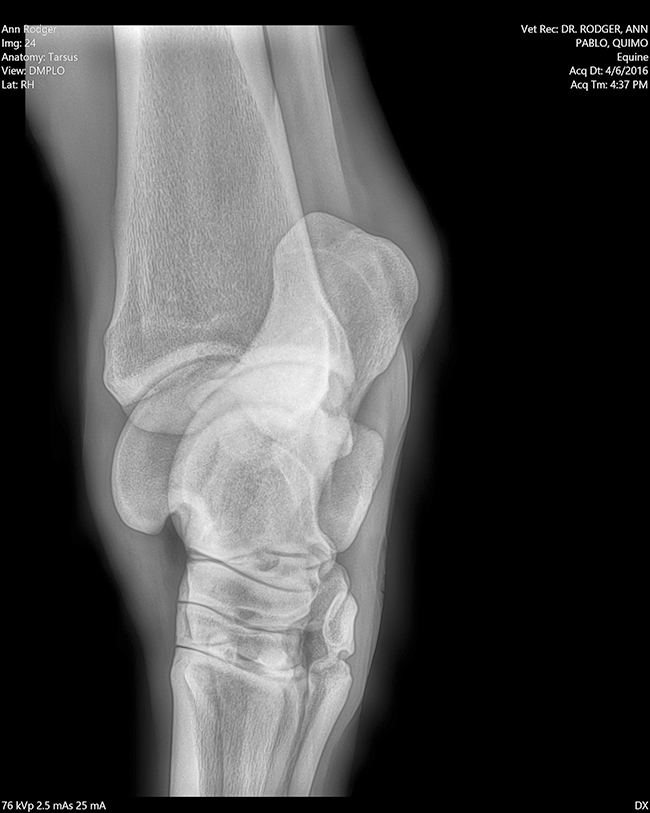

Radiología

Contamos con el equipo de radiología digital inalámbrico más avanzado del país, el cual permite obtener las mejores imágenes en el acto y compartirlas vía mail. Realiza radiografías de miembros, columna, cabeza, cuello y hombro.

Dra. Ann Rodger

Dr Ann Rodger Médica veterinaria egresado de la universidad de Bs.As. UBA

20 años de experiencia. Veterinaria FEI. A cargo de los caballos que participaron en Americano San Pablo 2008, Children Chile 2009, Juegos Panamericanos en Canadá 2015 y los Juegos Olímpicos Río 2016.

Veterinaria del concurso Haras El Capricho. Se especializó en UC Davis Universidad de California con el Dr. Jack Snyder; en Palm Beach con el Dr. John Steel; Mid Atlantic Equine Medical Center, New Jersey.